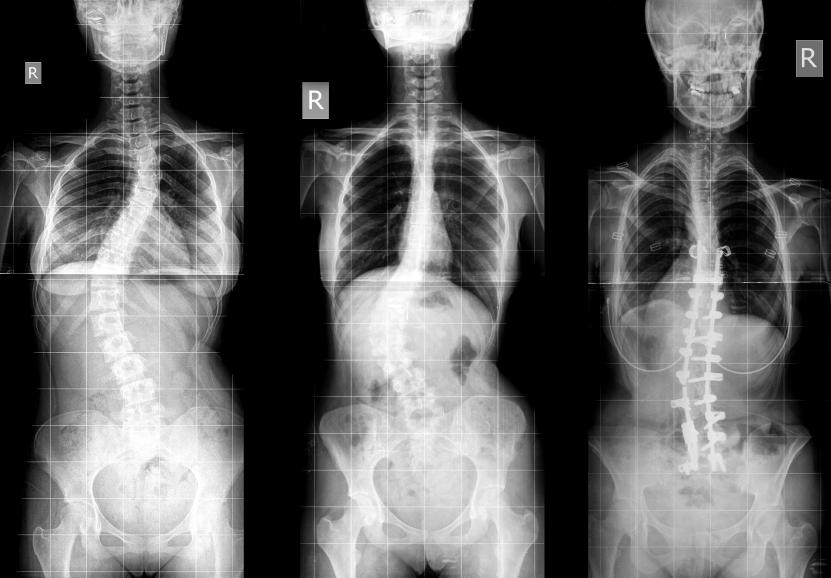

La escoliosis es un problema de salud que provoca una curvatura de la columna vertebral que puede darse en forma de "C" o "S". De entre los tipos de escoliosis, la más común es aquella que tiene lugar sin una causa aparente, conocida como escoliosis idiopática. Este tipo de curvatura es más frecuente en niños, especialmente a la edad de 10-12 años, período en el que se crece más rápido, aunque también existe la escoliosis en adultos. En función del tipo de escoliosis, edad del paciente, la gravedad de la curvatura y otros factores se llevará a cabo el tratamiento más adecuado para corregir la desviación de la columna.